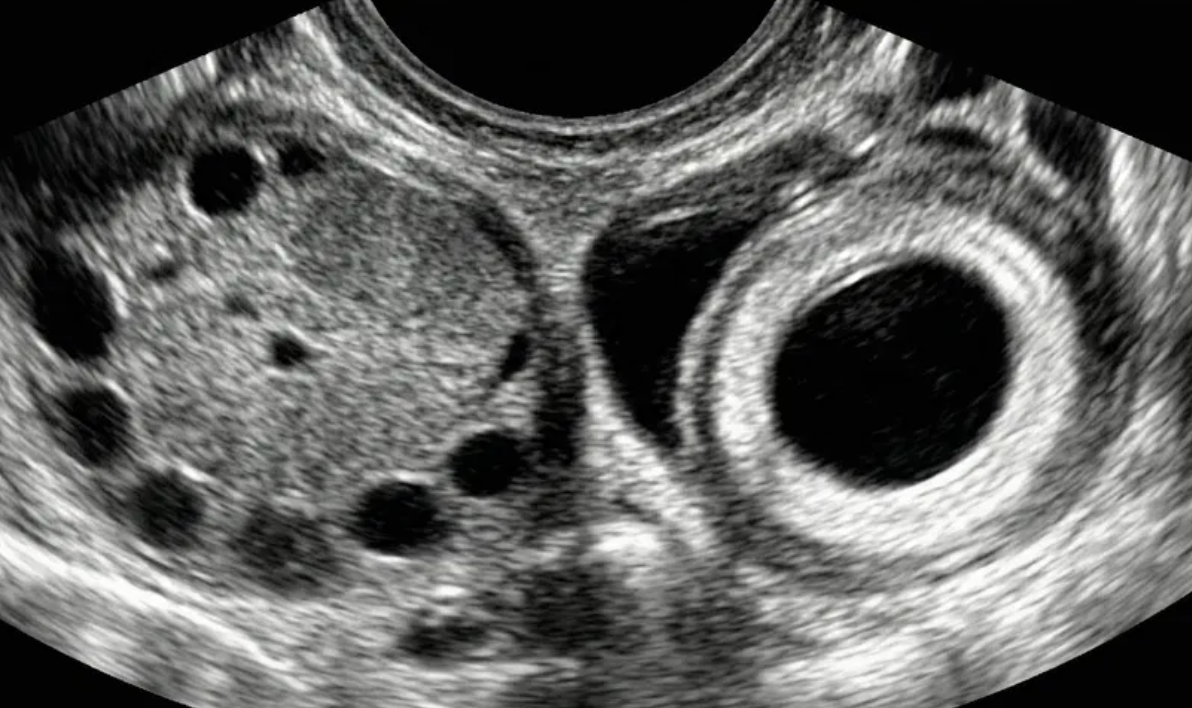

Gestação ectópica (US)

Ferramenta educacional baseada no NICE guideline NG126 (2019, atualização 2023), com abordagem conservadora. Ajuda a reconhecer sinais ultrassonográficos de gestação ectópica tubária e a lembrar a necessidade de correlação clínica e laboratorial.

Indica ectópica tubária (USTV)

Alta probabilidade (USTV)

Possível ectópica (USTV)